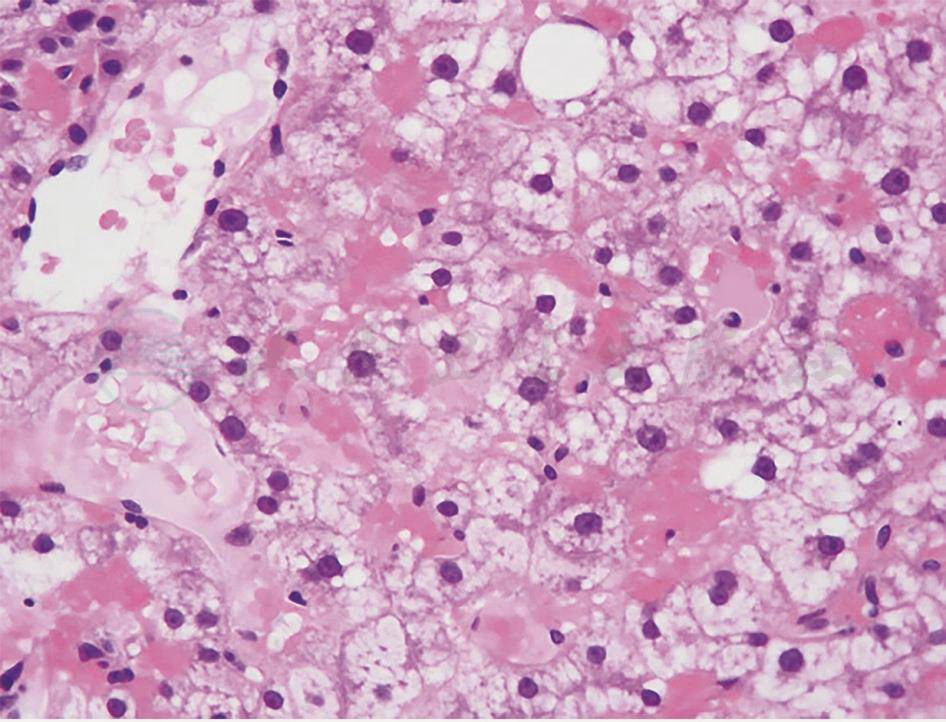

肝脏穿刺病理(图2):一条可见肝细胞胞浆空亮,胞膜清晰增厚,另一条汇管区不明显,可见肝细胞增生伴肝窦扩张充血,灶性纤维组织增生。免疫组化:肝型脂肪酸结合蛋白(liver-fatty acid binding protein,L-FABP)(-),CD34(血管+),CK19(少量+),C反应蛋白(+),Ki-67(5%阳性),GS(+),Hsp70(-),GPC3(-),B-cat(膜 +),SAA(-)。特殊染色:网染(网状纤维增生),过碘酸希夫(periodic acid-Schiff,PAS)染色(+)。

图2 肝脏穿刺病理(HE染色,100×)